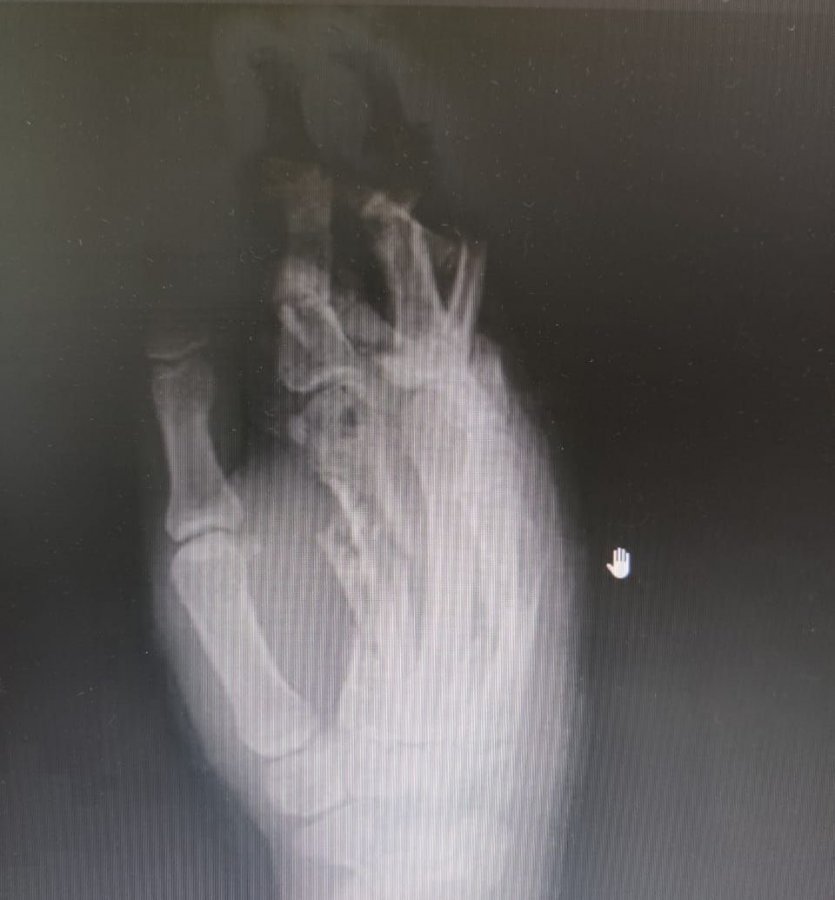

«Девушка поступила с размозжением мягких тканей кисти руки и фаланг пальцев. В результате операции выполнена фиксация переломов фаланг пальцев с помощью специального аппарата и проведена хирургическая обработка ран», – рассказал заведующий травматологическим отделением Константин Смирнов.